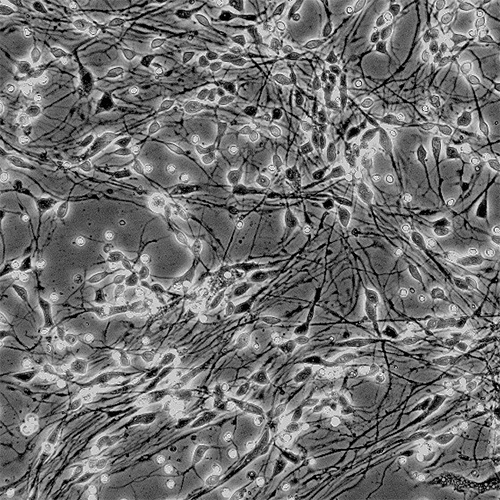

Cellular models

NEUROFIT has developed a functional neuronal assay that accumulates extracellular Aβ. The system is tailored to assess the efficiency of Aβ lowering drugs such as BACE inhibitors. In parallel, the assay provides also information about the potential safety or neurotoxicity of the tested drug.